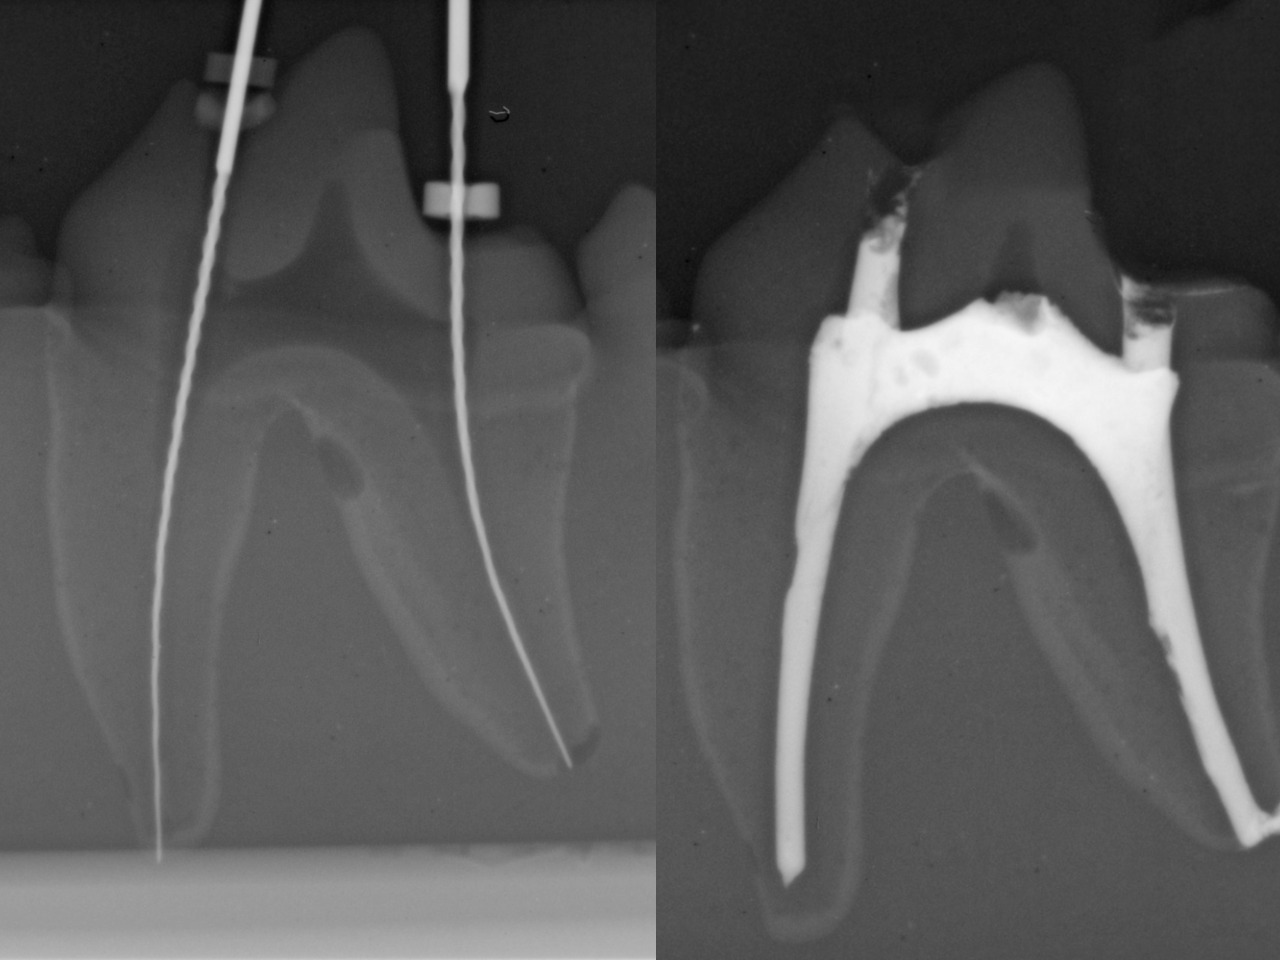

Veterinary endodontic training has long relied on extracted teeth and cadavers, making learning inconsistent, unpredictable, and impractical. GAIA changes that.

Our Endodontic Training Model provides a standardized, repeatable, and hands-on experience, ensuring that every student and practitioner can refine their skills in a controlled, structured environment—just like in real clinical cases.